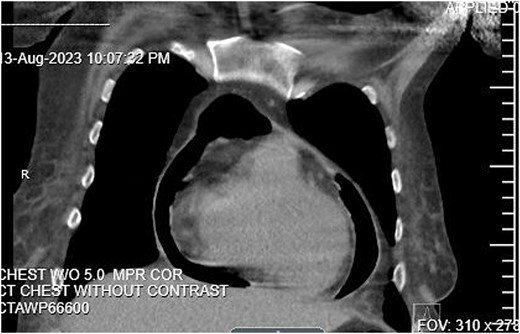

An echocardiogram revealed an EF of 45%–50%. The IVC was dilated and collapsed less than 50% with a sniff, suggesting high right atrial pressure. There was concern that a gastro-pericardial fistula caused the pneumopericardium, so another CT chest with oral contrast was ordered. The CT demonstrated the passage of the oral contrast into the pericardial space, confirming the gastro-pericardial fistula (Fig. 2).

CT Chest with oral contrast demonstrating gastropericardial fistula.